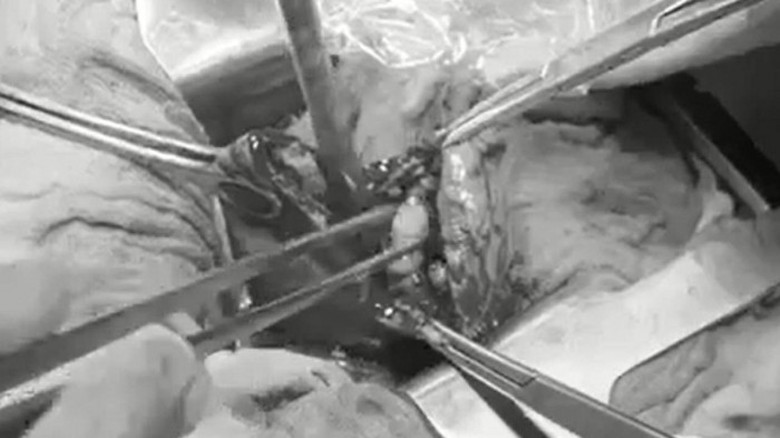

Bác sĩ phẫu thuật gắp sỏi mật cho bệnh nhân

Trực tiếp phẫu thuật cho bệnh nhân, BS. Thưởng cho biết: “Phẫu thuật cắt túi mật có thể được tiến hành bằng phương pháp mổ nội soi hoặc mổ mở. Ở bệnh nhân này ban đầu chúng tôi chọn phẫu thuật nội soi cắt túi mật, nhưng sau đó phải chuyển sang mổ mở do túi mật viêm căng to, tổ chức xung quanh dính nhiều, có rất nhiều sỏi. Mở túi mật của bệnh nhân chúng tôi đã gắp ra 54 viên sỏi, viên sỏi lớn kích thước 27mm”.